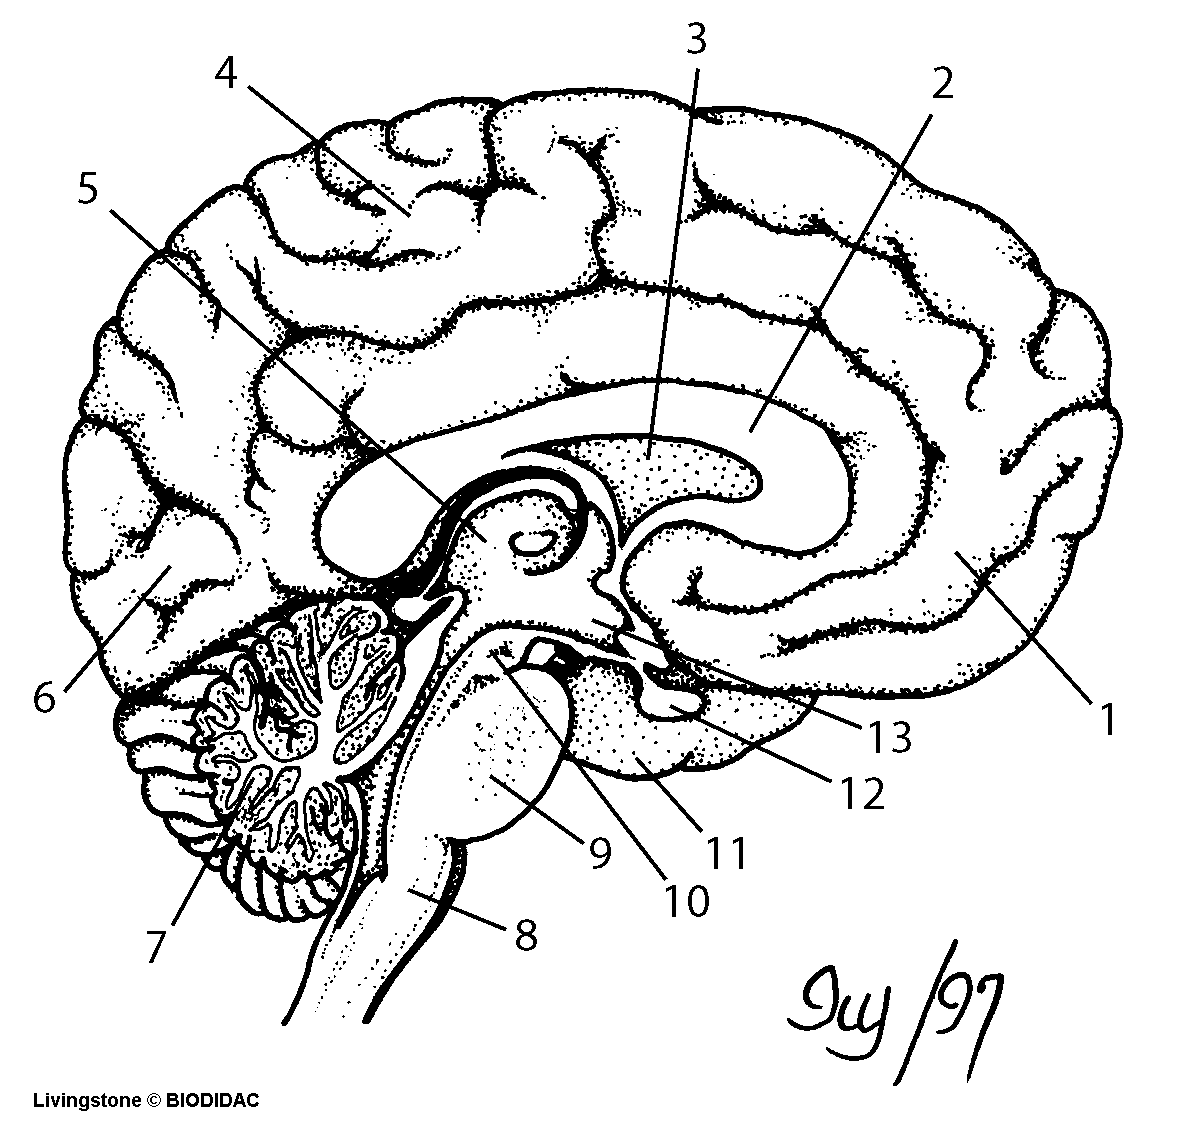

spec.expres.uaDownload Blank Brain Diagram - Cognitive Science: Questions And Answers

spec.expres.uaDownload Blank Brain Diagram - Cognitive Science: Questions And Answers

Brain Diagram Blank

healthiack.combrain diagram blank drawing labels human anatomy diagrams 1291 without labeled line simple midsagittal getdrawings healthiack paintingvalley

Blank Brain Diagram

ar.inspiredpencil.comBlank Diagram Of The Inside Of The Brain Blank Brain Diagram System

ar.inspiredpencil.comBlank Diagram Of The Inside Of The Brain Blank Brain Diagram System

www.pinterest.combrain anatomy diagram blank drawing coloring human inside system choose board